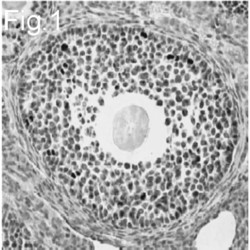

LS-C355638 IHC

Full details

Method:

Other validation